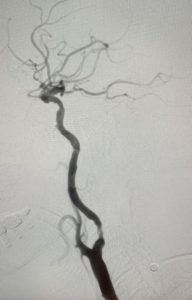

經過1小時的血管急救,所有血栓都被移除,羅先生的右頸和腦部血管都給順利打通,腦部缺血情況立即得到改善。血栓被吸取後, 腦血管外科醫生發現羅先生的右頸內動脈有嚴重血管狹窄的情況,這個狹窄就是羅先生中風的主要原因。醫生因此植入血管支架來重新擴張狹窄的血管,以防止羅先生將來中風復發。全身麻醉清醒後,羅先生的大腦意識和手腳活動能力即時好轉,他其後再被送回另一間公立醫院繼續康復治療。

| 血栓被吸取後, 右頸和腦血管都給順利打通,腦部缺血情況立即得到改善 | |